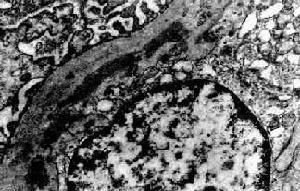

2.Ⅱ型 被稱為自身免疫性疾病在電鏡下可觀察到沿著基底膜的層黏蛋白層呈均勻一致的帶狀沉積,此型又稱為緻密物沉積病(DDD),還常伴有上皮下類似駝峰樣沉積物沉積PAS染色有時可見毛細血管襻上呈條帶狀深染Ⅱ型主要被認為與鏈球菌感染有關由於鏈球菌與腎臟抗原有交叉反應,可引起抗體介導的腎損害。Ⅱ型常並發血漿低C3水平因為部分患者血中存在補體激活物,一種自身抗體,也稱致腎炎因子或C3腎炎因子直接抗C3bBb,改變C3旁路轉化,通過與轉化酶結合,阻止一些正常抑制因子如H因子等作用,增加了補體的活化及消耗。C3腎炎因子在Ⅰ型和Ⅱ型MPGN中多見,尤其是在Ⅱ型中更為常見。部分與脂質營養不良有關。由於MPGNⅡ型主要是基底膜的損害,如有大量的緻密沉積物沉積在基底膜上,這些沉積物可以激活補體,補體被一些特殊物質如核糖酶激活,通常又可以激活旁路途徑,使C3腎炎因子繼發性持續增加而導致血中補體C3的下降。Ⅱ型MPGN中。70%的患者補體C3和B因子降低。

電鏡下系膜細胞和系膜基質增生伴系膜插入,即增生的系膜細胞和系膜基質插入到基底膜和內皮細胞之間。系膜基質和基底膜形態相似,因而看上去似有兩層或多層基底膜,這就是光鏡下所見的雙層或多層的形態,一層是原有基底膜,另幾層是插入到內皮細胞和基底膜之間的系膜基質。腎小球內可見電子緻密物。Ⅰ型大量電子緻密物位於基底膜內皮側及系膜區域,少量見於上皮下;Ⅱ型電子緻密物的電子密度較Ⅰ型明顯高,沿基底膜緻密層呈帶狀分布。